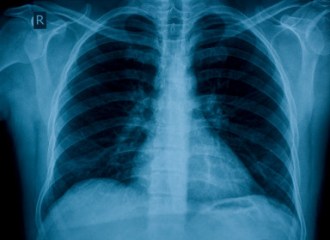

Tb Skin Testing

The Tb Skin Test is administered to determine if someone has developed an immune response to the bacterium that causes tuberculosis (Tb). A Tb Skin Tests must be read 48-72 hours after the injection. The California Department of Social Services has stated that anyone working in a Community Care facility is required to have a Tb, or PPD,…

The LIC 503 is required by the California Department of Social Services as part of the application process to work in a Community Care facility. It is used during the hiring process to verify the health of the applicant. It requires completion and signature by a physician. Health Screening (LIC 503)